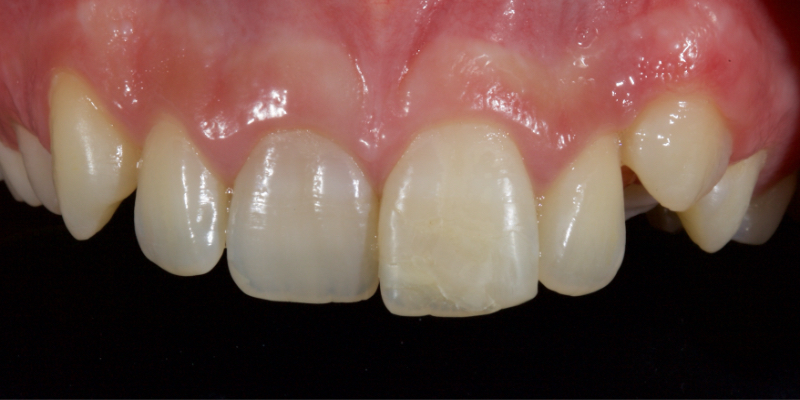

Historically, discolored anterior teeth were treated with indirect ceramic restorations, such as crowns or veneers. This can be illustrated in the case shown in Figure 1, where the discolored left central incisor (2.1), along with two other incisors, was treated with lithium disilicate ceramic veneers (Fig. 2). More recently, direct composite materials that incorporate specialized “opaquers” have also been utilized for treatment.

This article explores a more modern, minimally invasive approach to discolored non-vital teeth using the “modified walking bleach” approach. Figure 3 (before treatment) and Figure 4 (after treatment) show an example of this highly conservative approach.